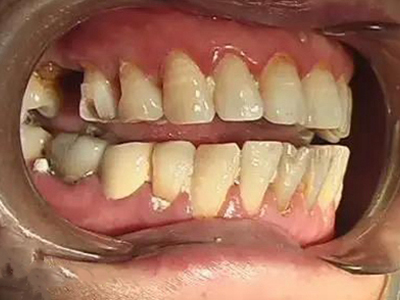

酸蚀症后排牙齿大量缺损图

酸蚀症患者的后排牙齿可发生大量缺损,一侧牙齿遗留圆盘状牙根,形似被切割,另一侧牙齿有大量凹陷坑洞,部分牙齿颜色发黑或呈黄褐色,其发生与长期接触酸性物质有关。